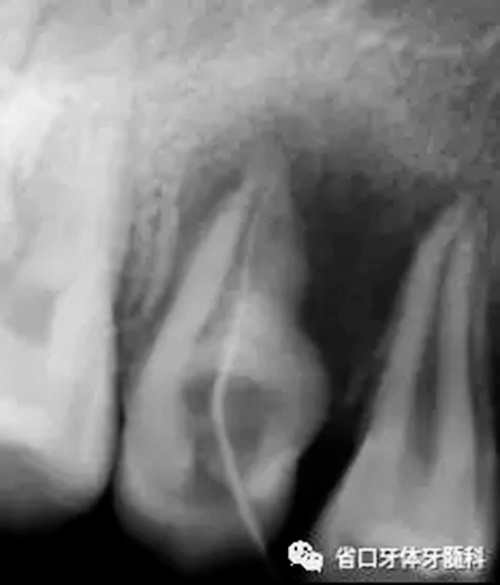

圖2 根尖片(2016-3-19),15未完全萌出,形態(tài)異常, 根尖周和根側(cè)方見低密度影,牙槽骨破壞

圖3 CBCT(2016-11-13):15由髓腔至根管內(nèi)見團(tuán)塊阻射影像,阻射影中央為透射影,根尖1/3處見根管膨大,腭側(cè)牙槽骨破壞,根尖周低密度影范圍大,上頜竇黏膜增厚。